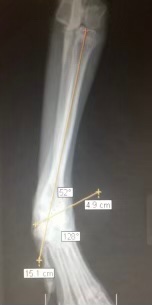

Surgical correction of angular limb deformity in a young dog. Asynchronous injury to the growth plates of the bones results in an angular forelimb, causing joint pain and limb dysfunction if left uncorrected. (See thread for post-op images)